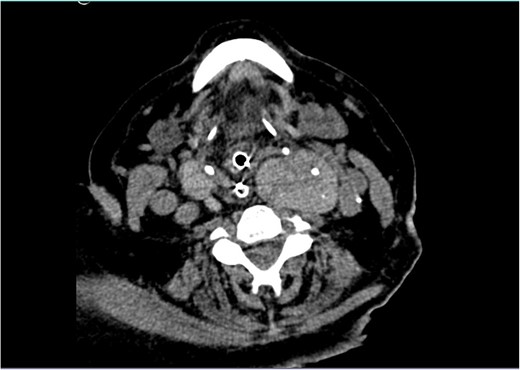

The patient remained monitored but a few hours later progressed with stridor and aggravated hypoxemia. An urgent nasopharyngoscopy was performed which showed significant laryngeal oedema and bulging of the posterior wall of the left hypopharynx. Despite systemic corticoid therapy, a decreased level of consciousness and desaturation lead to an orotracheal intubation. An urgent neck CT revealed a large multinodular goitre (RL 46 × 36 × 91 mm and LL 48 × 51 × 103 mm), with the superior pole of the left lobe ascending to the angle of the mandible, in a suprahyoid position, posterior to the submandibular gland (Fig. 1). The thyroid was extrinsically compressing the trachea and larynx, causing a deviation of the respiratory column to the right and narrowing of its lumen (Fig. 2). There was no apparent invasion of adjacent structures.

External compression of the thyroid and larynx by the mass with narrowing of its lumen.